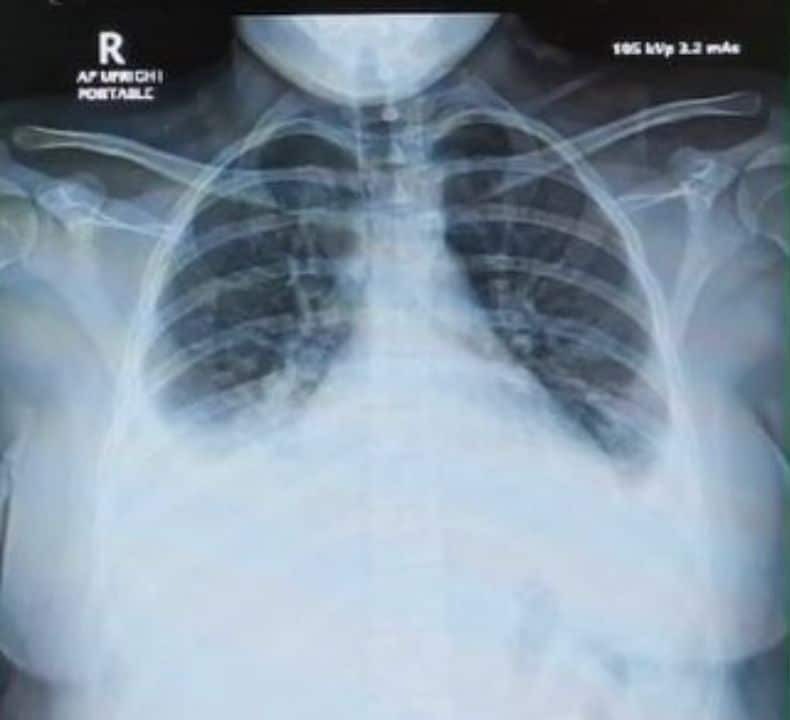

ယၢမ်းလဵဝ် ၵူၼ်းၼုမ်ႇၵေႃႉၼၼ်ႉ ယူႇသႃႇမႃးၶိုၼ်းယဝ်ႉသေတႃႉ မေႃယႃၶဝ်ၵူတ်ႇထတ်းႁၼ်ဝႆႉ မီးၵွၼ်ႈလိူတ်ႈၶၢဝ်ၼမ်ဝႆႉ။ ၾၢႆႇၼိုင်ႈၵေႃႈ မၼ်းၸၢႆး ၵိုင်ႉၵၢင်ႉ သုတ်ႇၺႃးသႅဝ်ဢၢႆလူမ်း ဢၼ်မီးၵွင်ႉၾုၼ်ႇၵႂၼ်း PM 2.5 ၼမ်ႁႅင်းလူၼ်ႉၵႂႃႇလႄႈ လႆႈၸပ်းတၢင်းပဵၼ် ပွတ်ႇၵႆႈ (acute eosinophilic pneumonia) ၵႂႃႇ ၼႆယဝ်ႉ။